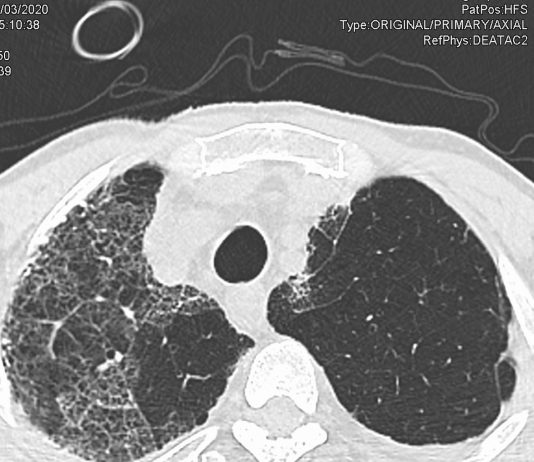

61-years-old male

patient admitted to the ED for severe dyspnea, confusion on March 3. Bedfast after a recent upper respiratory

infection. Medical history: DM type...